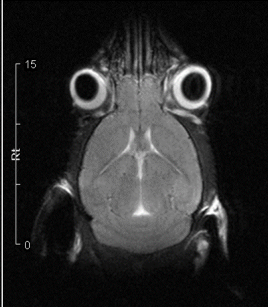

mri_fish

Killifish femal eggs